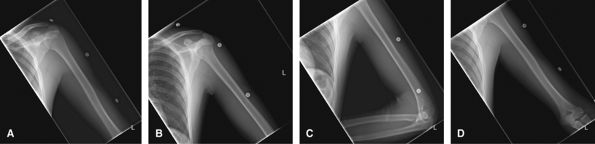

Humerus

To assess for trauma, infection, mass, or foreign body.

Both the shoulder and elbow should be included on the study in both

projections, but they should not be over interpreted on such limited

views.

![]() |

Figure 12 (A) AP to include shoulder joint. (B) Lateral to include shoulder joint. (C) AP to include elbow joint. (D) Lateral to include elbow joint.